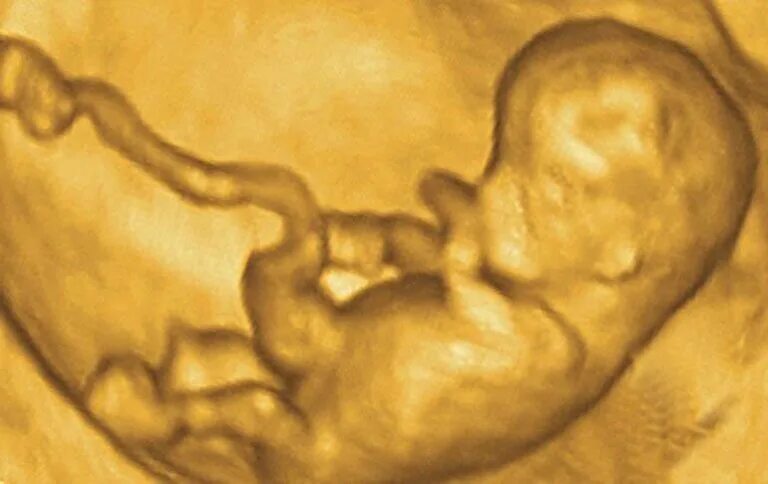

Ребенок в 13 недель